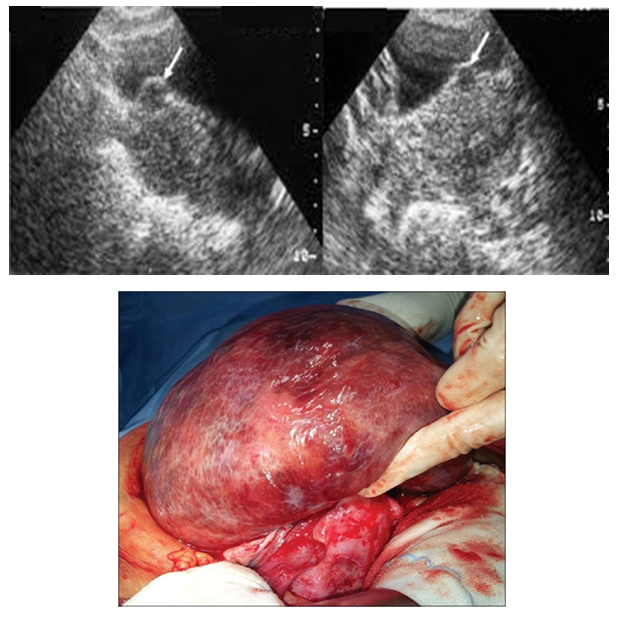

Metastatic Uterine Leiomyosarcoma in a Nullipara with Primary Infertility: A Case Report

Okechukwu B. Anozie, Johnbosco I. Nwafor, Chidi U. Esike, Chukwuemeka I. Ukaegbe, Richard L. Ewah, Emeka O. Onwe, Justus N. Eze, Sunday U. Asogwa

International Journal of Innovative Research in Medical Science·November 1, 2019